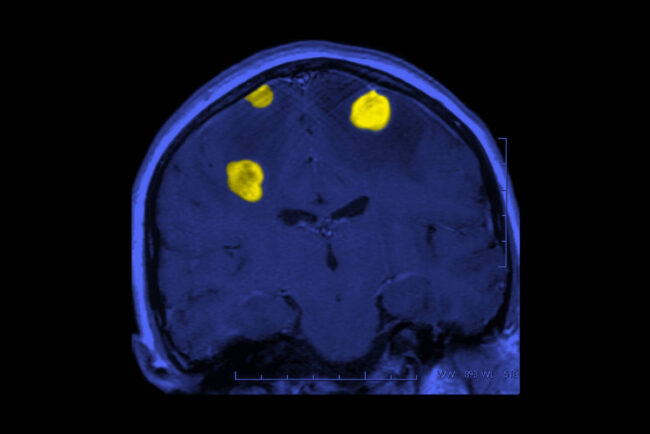

Dan esperanza a pacientes con tumores cerebrales

Los tumores cerebrales ocupan el lugar 19 entre todas las neoplasias, y el 10 entre las más letales. A nivel mundial, cada año se diagnostican cerca de 300 mil nuevos casos, que corresponden al 2.5% de la mortalidad por cáncer. En Estados Unidos están poco estudiadas la incidencia y prevalencia de estas neoplasias, pero se…